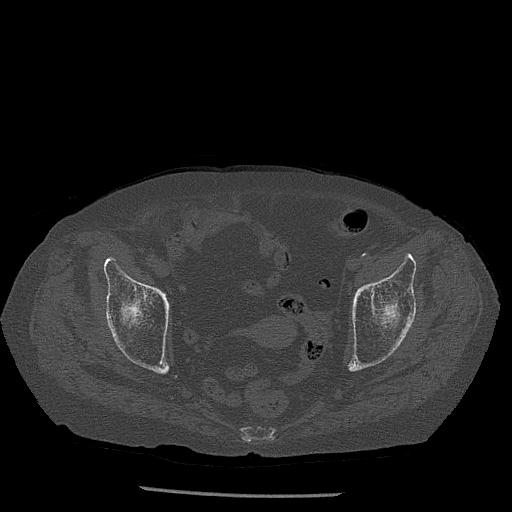

100703 1/27 両股正面+軸 1/29 両股正面+軸 94歳女性 パンソンロン